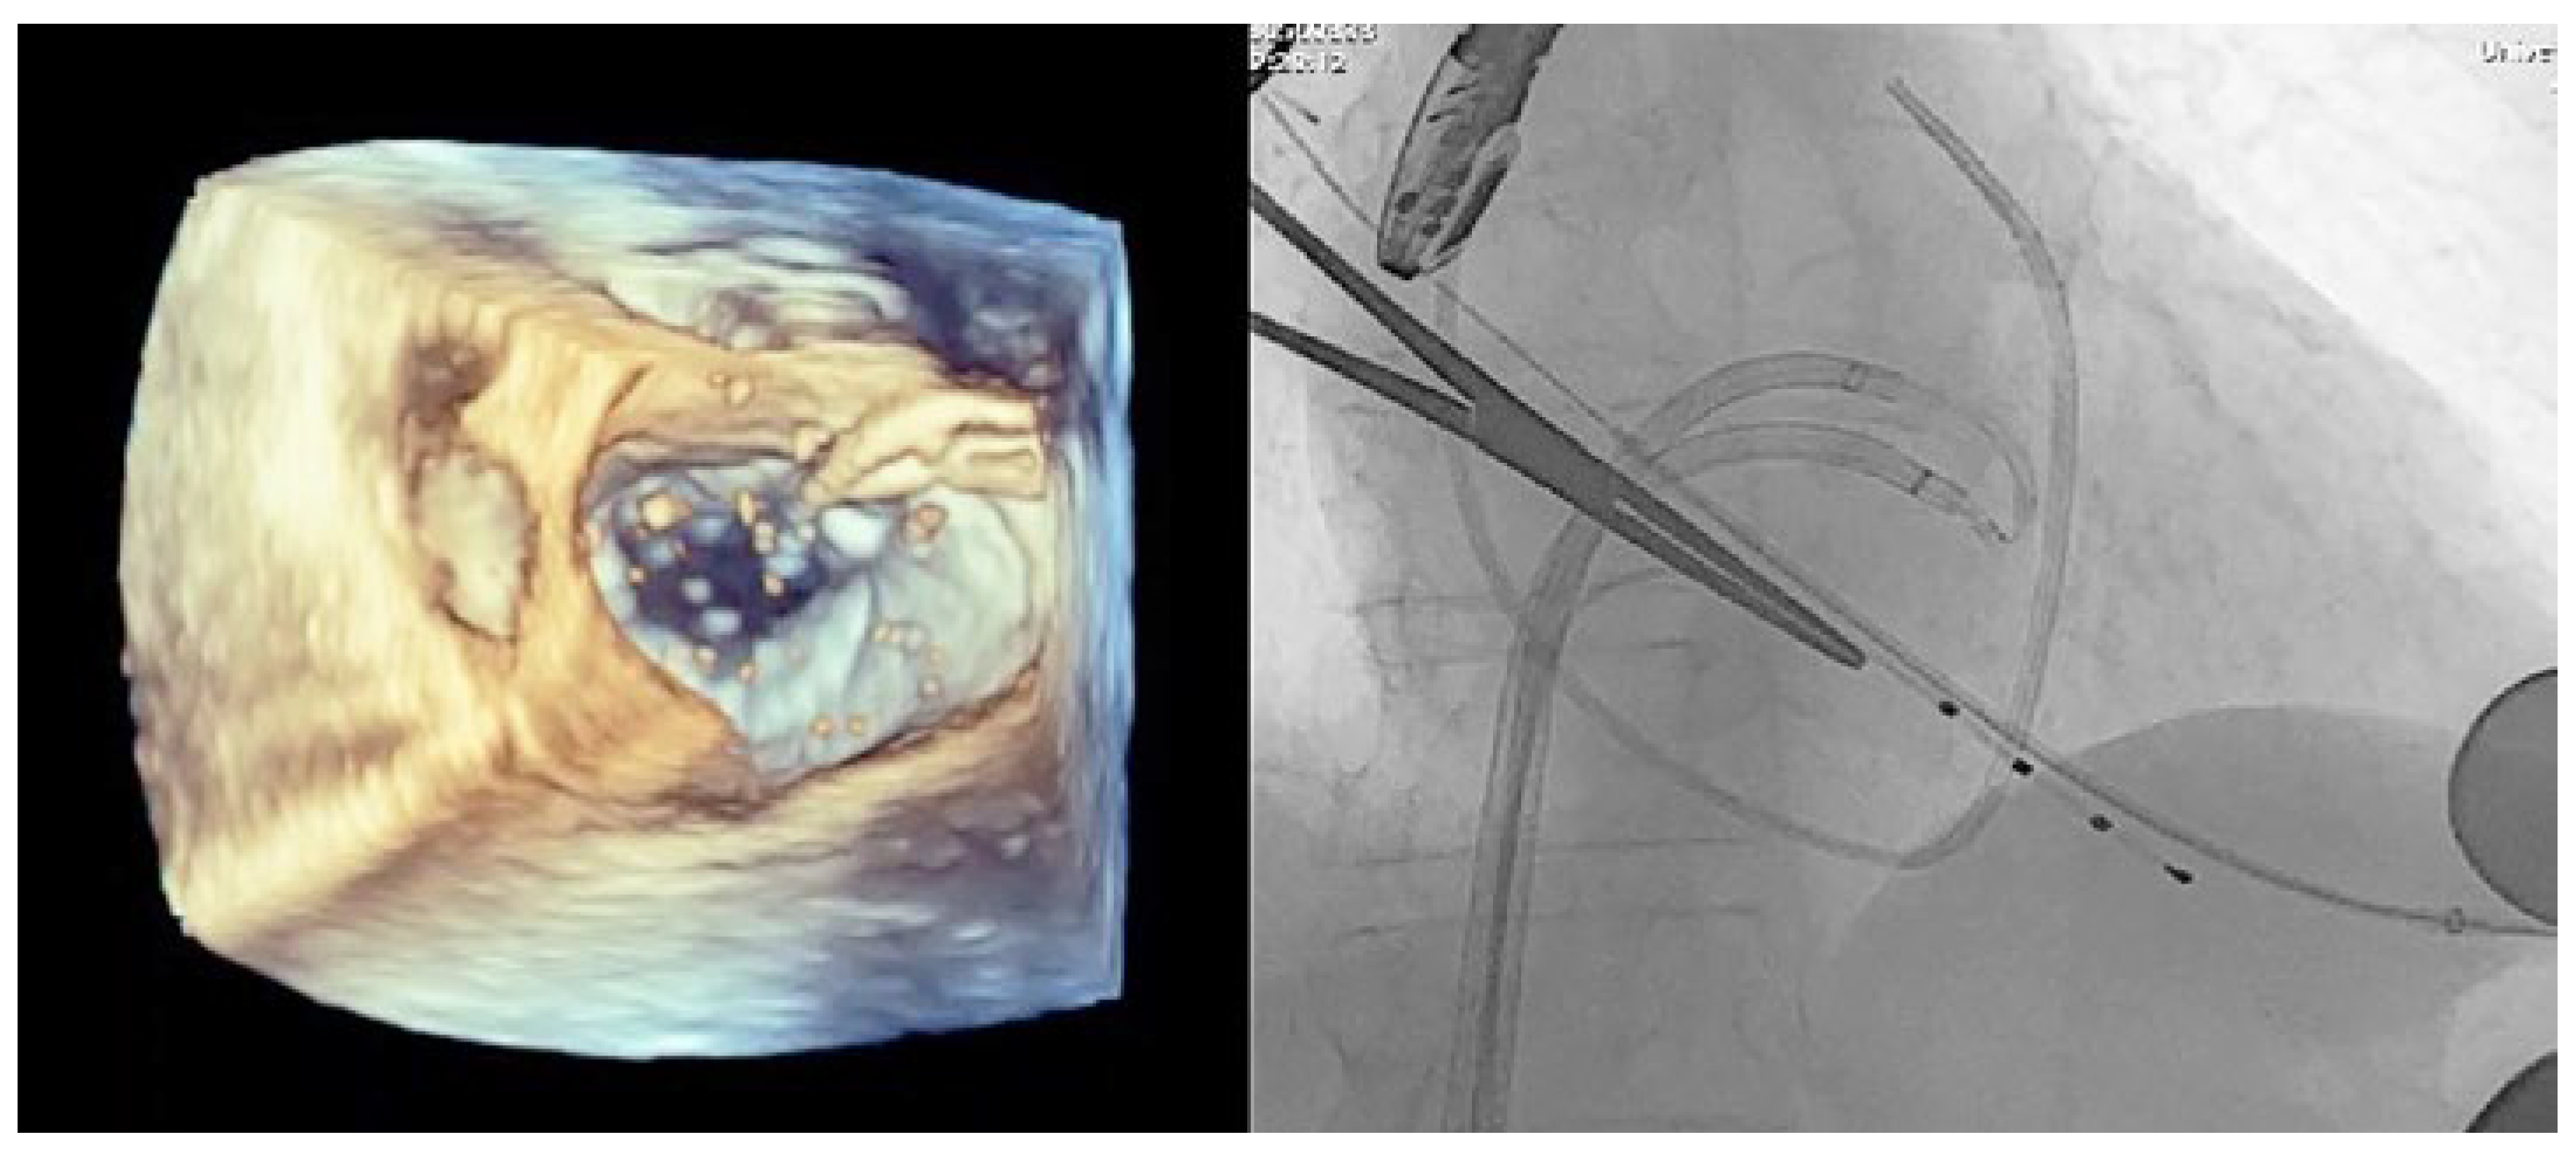

Case Description

Operative Procedure